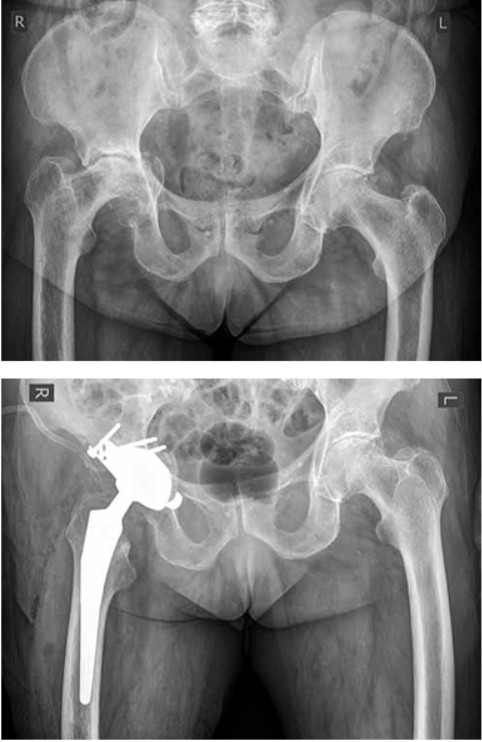

Нами детально изучены результаты эндопротезирования тазобедренного сустава с использованием системы с ДМ фирмы SERF (Франция) у 22 пациентов: 15 женщин и 7 мужчин. Среди причин эндопротезирования превалировали переломы и ложные суставы шейки бедренной кости — у 8 пациентов, средний возраст которых составил 64 года (рис. 1). Во всех случаях был использован стандартный чрезъягодичный доступ по Хардингу. У наших пациентов в течение года после имплантации эндопротезов с двойной мобильностью вывихов не зарегистрировано. Отмечен значительный прирост показателей по шкале Харриса (в среднем с 34,4 до 82,3 баллов). По данным литературы, частота вывихов головки эндопротеза после эндопротезирования по поводу переломов шейки бедренной кости выше по сравнению с заболеваниями тазобедренного сустава [12]. Так, например, в исследовании R. Iorio с соавт. средняя частота вывихов при переломах шейки бедренной кости составила 10,7%, что в пять раз выше, чем при коксартрозе [21].

Рисунок 1. Рентгенограммы пациентки П., 75 лет: а — при поступлении: перелом шейки левой бедренной кости; б — имплантирован эндопротез левого тазобедренного сустава с двойной мобильностью

Figure 1. X-rays of patient P., female, 75 y. o.: a — at adimission: left femoral neck fracture; b — a left hip joint replacement using double mobility system